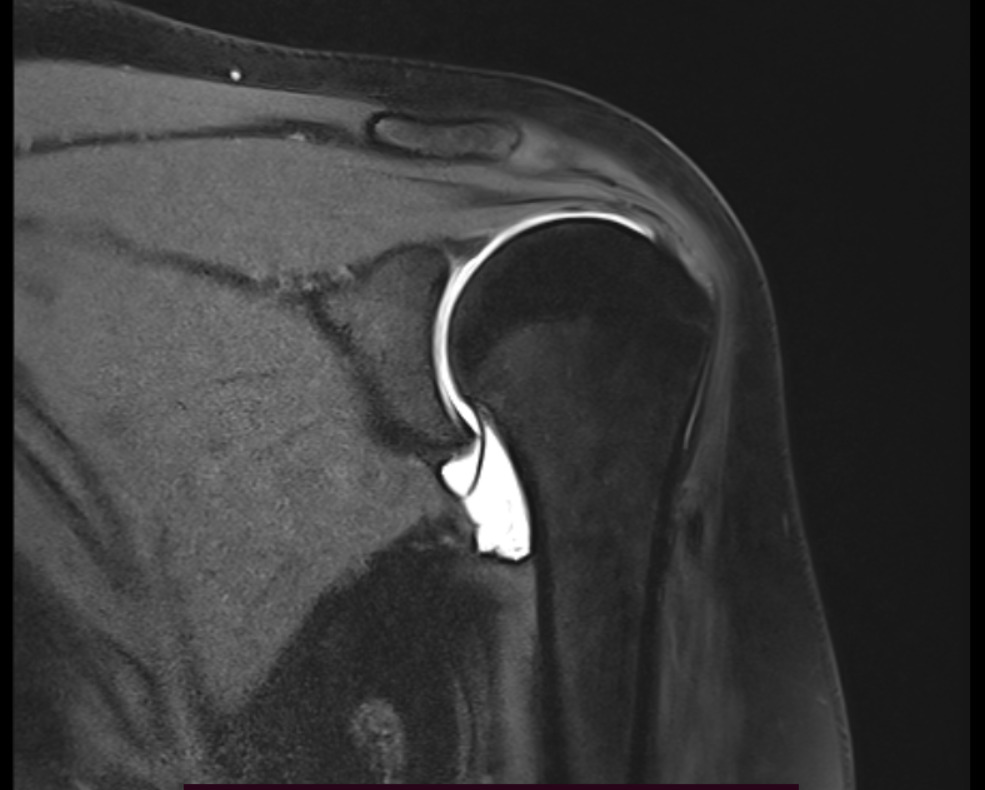

Une arthro-IRM peut être réalisée. Elle nécessite préalablement une injection d’un produit de contraste dans l’articulation en salle conventionnelle de radiographie. Immédiatement après l’IRM de l’articulation est réalisée. Comme pour toute ponction, il y a un risque très faible d’infection bien que toutes les précautions nécessaires pour l’éviter aient été prises. Dans ce cas il faut appeler le radiologue ou votre médecin prescripteur sans délai si votre articulation présente des symptômes inhabituels à type de douleurs, gonflement, s’il apparaît de la fièvre dans les jours qui suivent l’examen. Limitez les mouvements de votre articulation durant les 24 heures suivantes pour éviter la survenue de douleurs ou d’un épanchement (gonflement). Interrompez le sport et la kinésithérapie pendant 48 heures et 4 à 5 jours si une infiltration de cortisone a eu lieu.